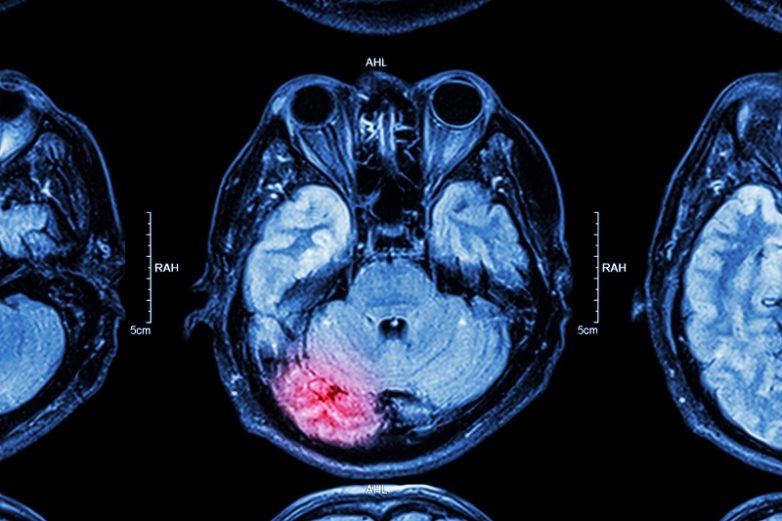

Нарушение мозговой деятельности

Причиной тремора в некоторых случаях может стать инсульт или черепно-мозговая травма. Справиться с проблемой поможет медикаментозное лечение в сочетании с отказом от кофеина, никотина и алкоголя.